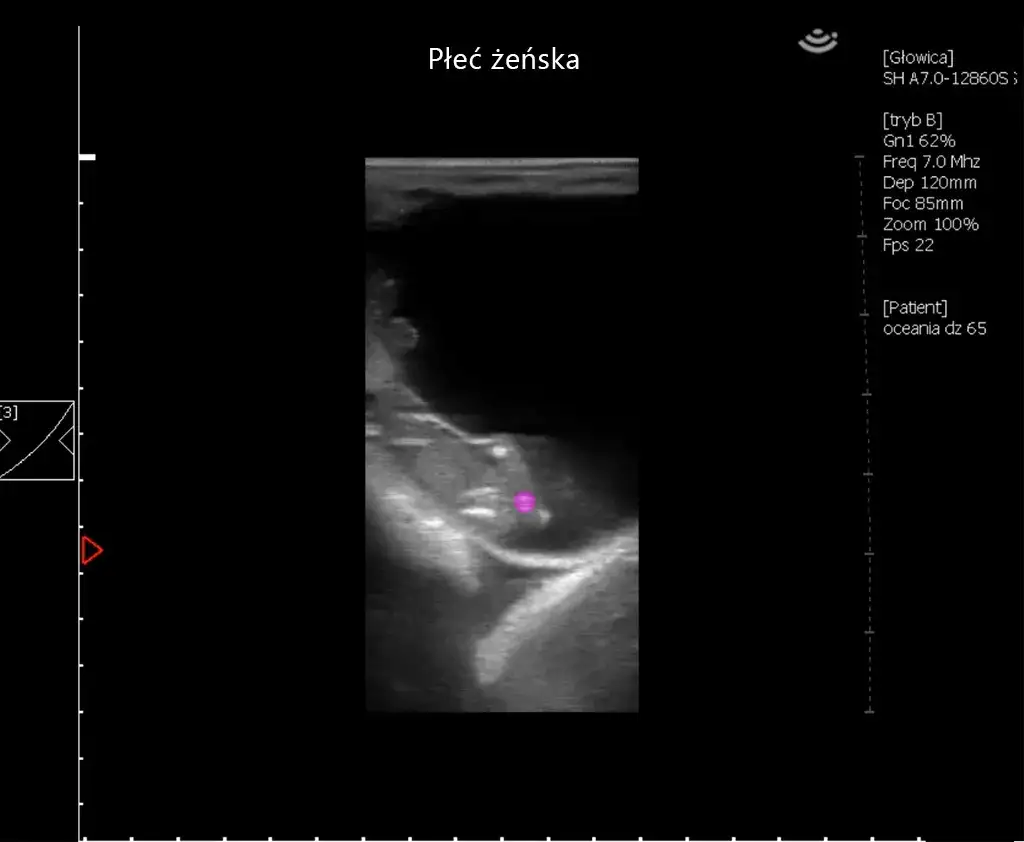

Badanie ultrasonograficzne (USG) to jedna z najskuteczniejszych metod potwierdzania ciąży u koni. Ultrasonografia działa na zasadzie wysyłania fal dźwiękowych do wnętrza ciała klaczy, które odbijają się od tkanek, tworząc obraz. Dzięki tej metodzie można wykryć mały zarodek już po około dwóch tygodniach od zapłodnienia, co daje prawie 100% pewności co do stanu ciąży. Co więcej, USG pozwala na wczesne wykrycie ciąż bliźniaczych, co jest istotne, ponieważ takie ciąże mogą stanowić poważne zagrożenie dla zdrowia klaczy oraz źrebiąt.

Wczesne rozpoznawanie ciąż bliźniaczych jest kluczowe dla zapewnienia zdrowia klaczy i źrebiąt. Objawy mogą być subtelne, ale najczęściej można je zidentyfikować za pomocą badania ultrasonograficznego, które powinno być wykonane około 15-16 dni po zapłodnieniu. W przypadku wykrycia dwóch zarodków, istnieje wysokie ryzyko, że ciąża nie będzie mogła być utrzymana. Właściciele powinni być świadomi, że wczesna interwencja w takich przypadkach jest niezbędna, aby zminimalizować ryzyko dla zdrowia klaczy.